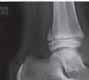

Podział złamań kości rosnących, tzw. złamań nasadowych: A – schematyczne przedstawienie klasyfikacji złamań; B – SH I (RTG, widok z przodu i z boku); C – SH II (RTG, widok z przodu i z boku); D – SH II (TK, widok z boku); E – SH III (RTG, widok z przodu i z boku); F – SH IV (RTG, widok z przodu i z boku); G – SH V (RTG, widok z przodu i z boku).

Rozpoznanie

Objawy złamania to silny ból uniemożliwiający stanie i chodzenie, zniekształcenie obrysów stawu kolanowego przez krwiak i różnego stopnia przemieszczenie nasady kości piszczelowej. Należy dokładnie zbadać stan ukrwienia i unaczynienia kończyny pod kątem objawów uszkodzenia tętnicy podkolanowej i nerwu strzałkowego. Trzeba ocenić bolesność uciskową oraz napięcie w przedziałach powięziowych podudzia: przednim, bocznym, tylnym powierzchownym i tylnym głębokim. U pacjentów z podejrzeniem wzmożonego ciśnienia wewnątrzprzedziałowego należy wielokrotnie powtarzać badanie ukrwienia i unerwienia kończyny, a w razie zaistnienia wskazań wykonać bezpośredni pomiar ciśnienia w przedziałach. Powinno się zawsze podejrzewać możliwość uszkodzeń więzadłowych współistniejących ze złamaniem. Badania obrazowe to RTG w pozycji AP, bocznej i skośnej. Wykonanie badania TK może być konieczne w celu pełnej oceny rozległości

złamania. W przypadku podejrzenia uszkodzenia tętnicy podkolanowej należy wykonać angio-TK lub arteriografię.

Leczenie złamania bliższej nasady piszczeli w przypadku uszkodzenia typu 1 i 2 według Saltera i Harrisa leczymy nieoperacyjnie. Należy wykonać zamkniętą repozycję i unieruchomić w opatrunku gipsowym udowym w zgięciu kolana 30–60°, zapewniającym najlepszą stabilność odłamów. Okres unieruchomienia wynosi od 6 do 7 tygodni. Po tym czasie usuwamy gips i zaczynamy ćwiczenia zwiększające zakres ruchomości stawu kolanowego oraz wzmacniające siłę mięśnia czworogłowego. Ważne jest, by prowadzić częste kontrole stanu ukrwienia i unaczynienia oraz kontrole radiologiczne w celu wykrycia ewentualnych przemieszczeń odłamów. Złamania pierwotnie niestabilne lub wtórnie przemieszczone wymagają zamkniętej repozycji stabilizacji drutami K. Typ 3 i 4

Złamania rzepki i podudzia

złamania według Saltera i Harrisa wymaga leczenia operacyjnego w postaci otwartej repozycji i stabilizacji śrubami. Należy unikać krzyżowania metalu zespalającego z chrząstką wzrostową. Kończynę zgiętą w kolanie do 30° unieruchamia się w gipsie udowym na okres 6–8 tygodni. Po tym czasie rozpoczynamy ćwiczenia czynne poprawiające zakres ruchomości kończyny.